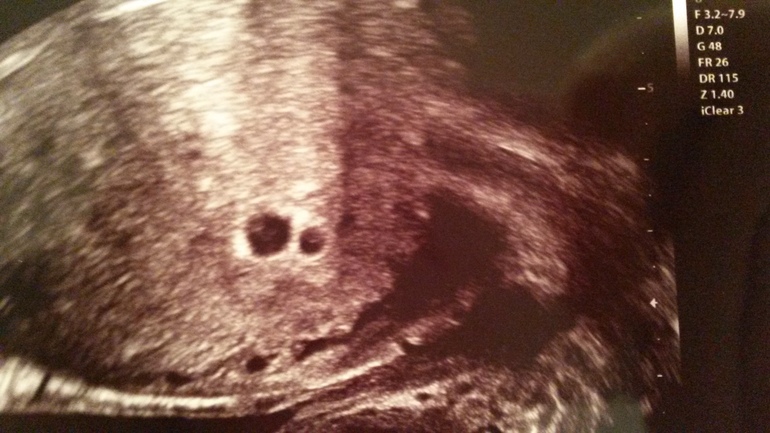

Там слева и справа по кружочку, ну один немного как прикрыт чем то что ли, но больше тут и подумать не на что!

И форма как прямоугольник,мои как треугольники были)

Да ЖМ были, мне вообще на том узи сказали что в большом два! То есть тройня) но оказалось нет, сейчас разница в 1 день между ними ставят. Думаю имплантация в разное время произошла.